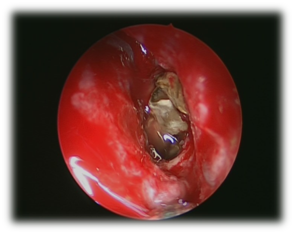

The commonest pathogens include Staphylococcus aureus, aerobic Gram-negative bacilli and anaerobes.10-14 These patients presented with headache, rhinorrhea, nasal obstruction, and blurred vision. The most common presenting symptom of sphenoid sinus disease is mainly headache. In the majority of previous reports, headache was nonspesific in location, quality and intensity.15 Physical examination and endoscopic finding may show mucopurulent secretion at the sphenoethmoidal area, edema of the sphenoethmoidal recess mucosa and polypoid tissue in the sphenoethmoidal recess. In CT scan of the sinuses (Figure 1) will show opacification in the sphenoid sinus, with mucosal wall thickening and air-fluid level. Management of these patients is medical treatment with antibiotic based on culture with topical corticosteroid and decongestant, the surgical intervention (endoscopic sphenoidotomy) (Figure 2) if failed medical treatment or patient presented with complications.

Figure 1 CT scans sinuses with homogenous opacification of both sphenoid sinuses.